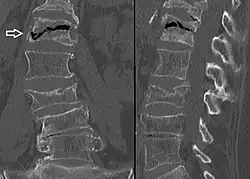

Compression fracture of the fourth lumbar vertebra post falling from a height.

Compression fracture of the fourth lumbar vertebra post falling from a height. -